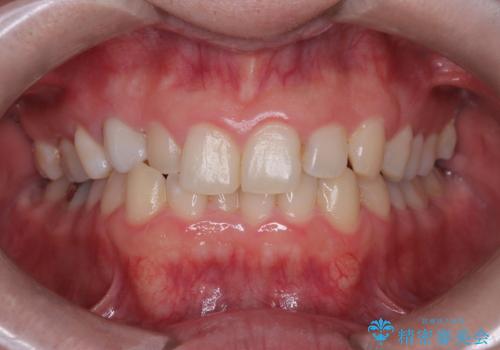

八重歯と正中のズレを解消!目立ちにくいワイヤー矯正で美しい歯並びへ

担当医 河口智英